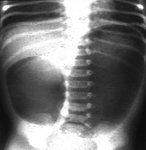

Radiografia abdominal de menino com dor abdominal aguda intensa, revelando fezes em todo o cólon e reto

Do acervo de Dr. KuoJen Tsao; usado com permissão